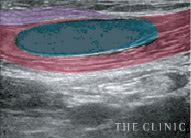

巨大なしこり

徐々に吸収されてなくなるはずのヒアルロン酸ですが、非常に大きなしこりが形成されてしまうこともあります。こちらは両胸ともに8cm以上のしこりが確認された症例です。

しこりの状態

しこりの大きさを把握することも重要ですが、ヒアルロン酸がどうなっているかで対処法が違ってきます。炎症や瘢痕化を起こしていないかなどもエコー検査から読み取ります。